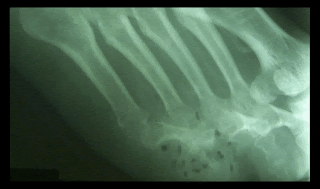

| Gas por infección en pie diabetico |

![]() |

| Arteria pedia calcificada. Hallazgo bilareral |